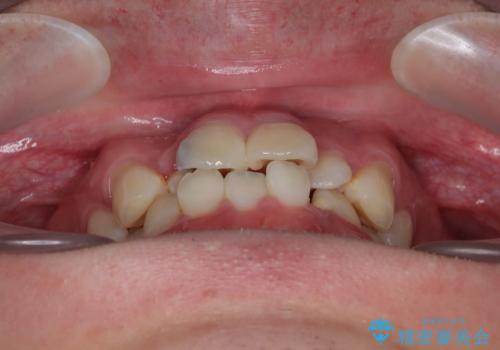

- 「歯並びがデコボコしていて、上下の中心がズレているのが気になる…」という悩みで来院された患者さまの症例をご紹介します。

初診時の状態

・上下ともに歯がきれいに並びきらず、がたつきが見られました。

・上下の前歯の中心(正中)がずれています。

・特に上顎の幅が狭いため、下顎の歯列も内側に入り込み、歯が並ぶスペースが不足していました。